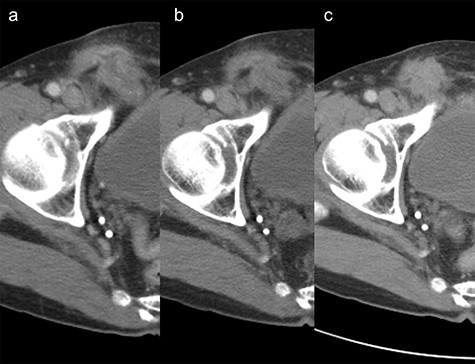

A 65-year-old man was admitted for the treatment of transverse colon cancer. He had a history of bilateral hernioplasty with mesh-plugs 6 years previously at another hospital. He had no complaints or findings on physical examination referable to the hernia repair. Fluorine-18 fluorodeoxyglucose positron emission tomographic (PET) scan showed positive findings in the transverse colon and in the right inguinal region prior to colon resection (Fig. 1a). Computed tomographic (CT) scan revealed a mass with indistinct margins in the same area highlighted on the PET scan (Fig. 1b). Inguinal lymph node metastasis was suspected and ultrasound-guided fine-needle biopsy performed, which showed no evidence of malignancy. After transverse colon resection, he was followed up with CT scans performed every 6 months. For three and a half years after the colon resection (Nine and a half years after hernia repair), the right inguinal region showed progressive changes (Fig. 2a–c). At 1 year after colon resection (7 years after hernia repair), fluid retention was observed, but by the second year (8 years after hernia repair), it was slightly reduced. After three and a half years after colon resection (nine and a half years after hernia repair), the fluid had resorbed completely, similar to the findings at 6 years after hernia repair. The patient had no complaints referable to the right inguinal region during follow-up.

Change over time after transverse colon resection in the right inguinal area on computed tomography scan. (a) 7 years year after hernia repair. (b) 8 years after hernia repair. (c) nine and a half years after hernia repair.